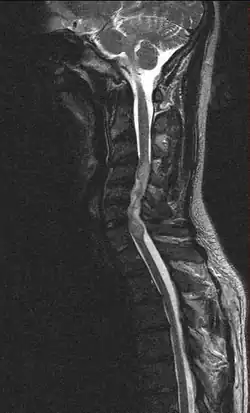

Ependymoma of the cervical spine, completely obscurating the spinal canal

Froin's syndrome is the coexistence of xanthochromia, high protein level and marked coagulation of cerebrospinal fluid (CSF). It is caused by meningeal irritation (e.g. during spinal meningitis) and CSF flow blockage by tumour mass or abscess.[1] Stagnation of the CSF within the thecal sac facilitates exudation from the tumour itself and activation of coagulation factors. A clinical test formerly used for evaluation of spinal stenosis is Queckenstedt's maneuver. Nowadays, a magnetic resonance imaging is used for identification of CSF flow obstruction. It often shows the prolongation of T1 and T2 signal in CSF caudal to a level of block.[2] This phenomenon is named after Georges Froin (1874–1932), a French physician who first described it.[3][4]